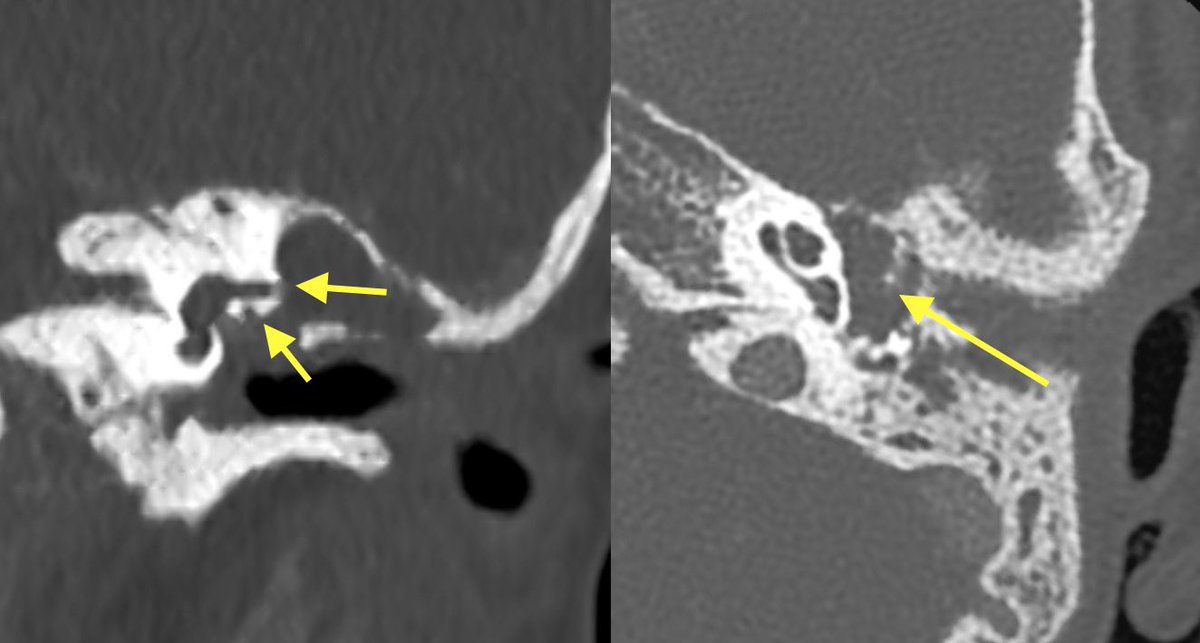

Initial T bone CT:

▶️Coalescence of mastoid air cells

▶️diffuse dehiscence of Tegmen tympani

▶️Middle ear ossicle erosions

▶️dehiscence of the roof of the EAC

▶️dehiscence of semicircular canals and tympanic segment of facial nerve

With findings this extensive it can be difficult to differentiate cholesteatoma from coalescent otomastoiditis

Helpful clues in cholesteatoma

💡 MORE MASS EFFECT (expansion of aditus ad antrum, displacement of middle ear ossicles with enlarged middle ear cavity)

💡 MORE EROSIONS (middle ear ossicles, facial nerve canal, semicircular canals)

💡 More likely to have retracted or ruptured TM

Cholesteatoma was favored in this case given the extent of erosions and lack of significant surrounding inflammatory change. However, symptoms were concerning for superimposed infection and meningitis